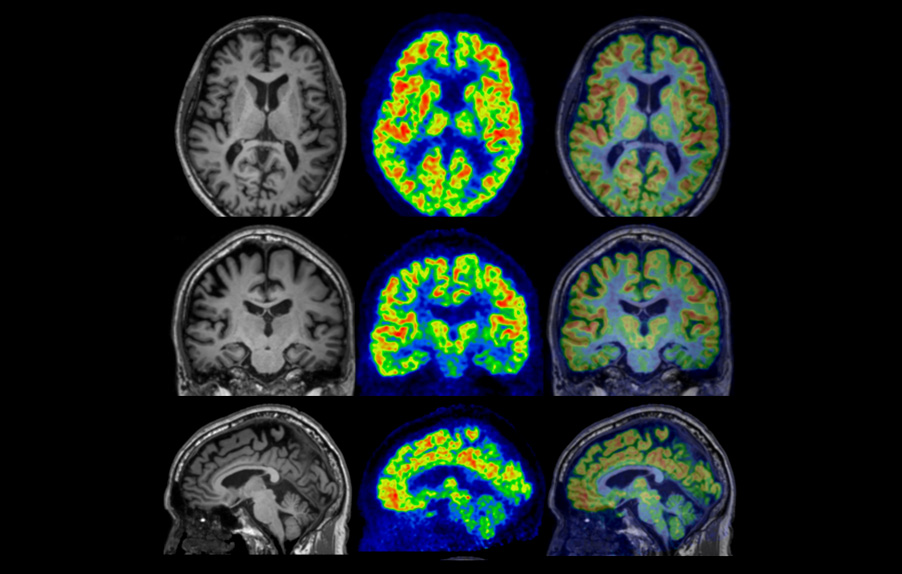

Fusion image of PET and MRI

Axial

Coronal

Sagittal

- Imaging protocol

- Injected dose: 2.87 MBq/kg, 18F-FDG

- Uptake time: 42 minutes

- Scan time: 30 minutes